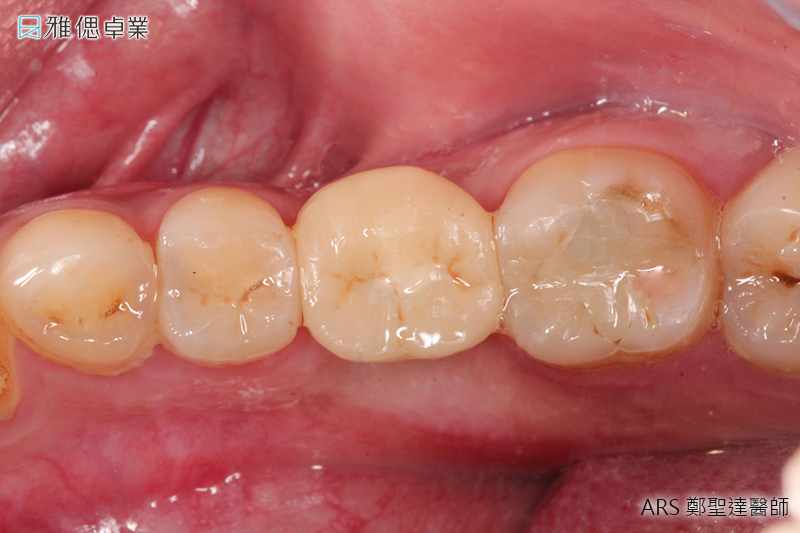

STEP6 正式牙套(正式假牙)完成

假牙會依據適合患者的咬合來做設計,若挑選全陶瓷假牙,它的高硬度及部分透光、美觀、咬合力量、高生物相容性、高密合度都會讓您照顧起來更加容易輕鬆。